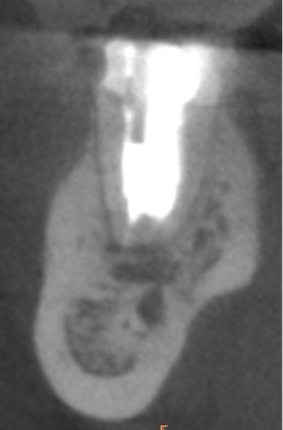

かぶせ物が不適であること(青矢印部)、近心根に根尖病巣があること(青枠部)、根充剤がかなり太いため(赤矢印部)歯質が薄くなっていることなど問題点がいくつかありましたが、他院で治療をしたばかりであり、また上記の条件から再治療には抜歯のリスクが非常に高いことから初診時は患者さんと相談し経過観察することになりました。